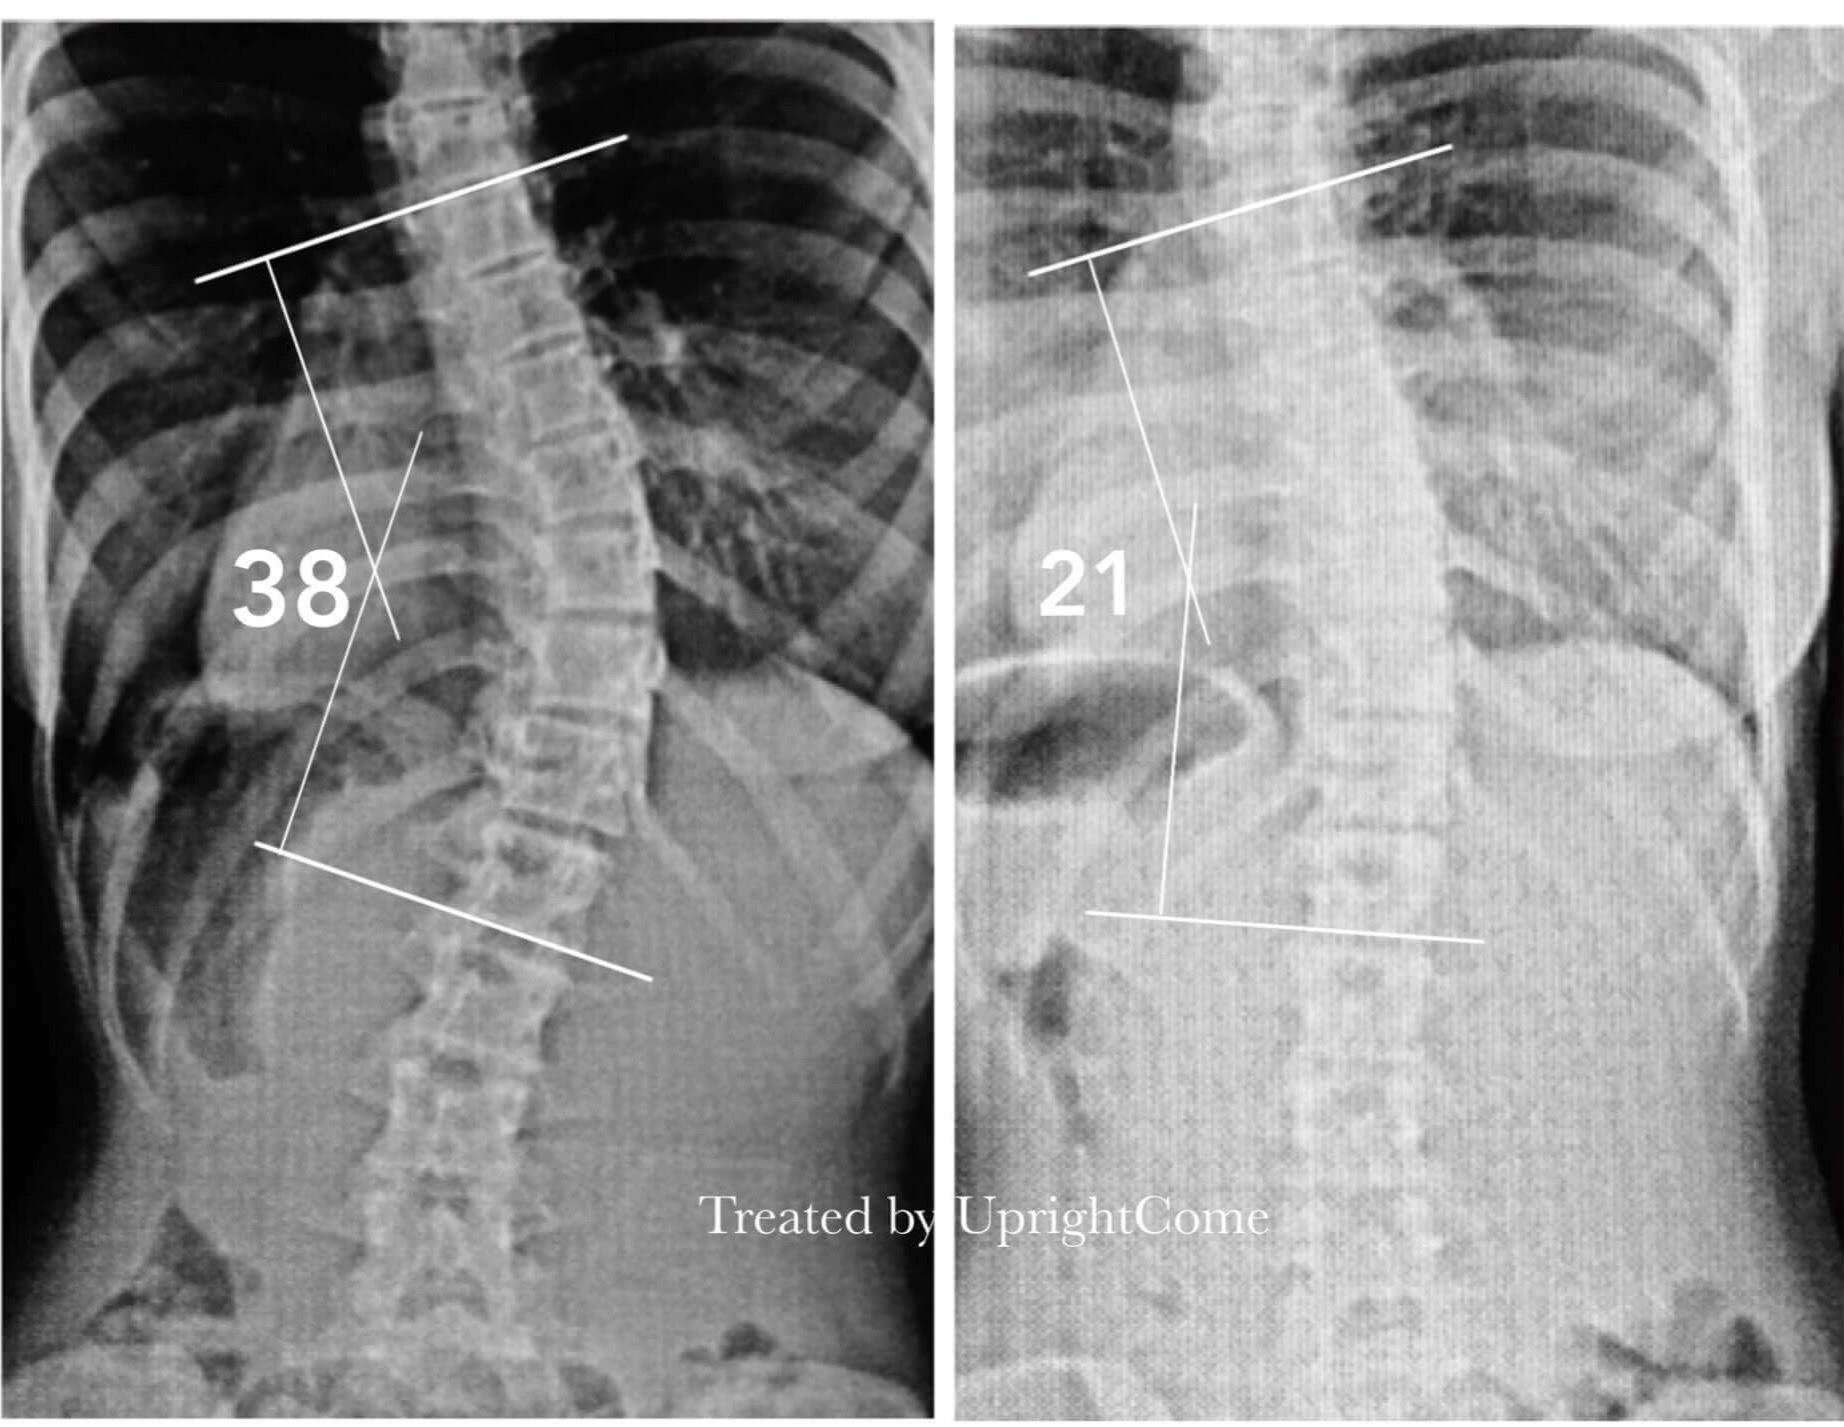

脊椎側彎是可以不用手術開刀治療的,挺立康有最專業的治療團隊,會依每個患者的情況不同,安排不同的治療方式,我們治療的脊椎側彎案例非常多,非常了解側彎患者的需求,會針對側彎患者的問題,提供專屬的矯正建議。